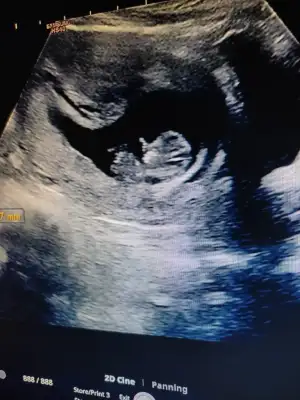

Omfalosel durumu vardı. Yani bebeğin karın duvarı kapanmadığı için iç organları karın boşluğu dışında yüzüyordu. Bu tüm bebeklerde gelişimin bir parcasi fakat 10. haftada organlar karın boşluğuna girerek karının iki yandan birleşmesi gerekirken bizim 10+5te halen kapanmamıştı. Doktorum da son tarih olarak 11+5 i bekleyip ona göre eğer kapanmadaydi ek tahliller yaparak deformasyonun boyutunu ve organ hasarlarına bakacaktı. Ama gerek kalmadı kapanmış....